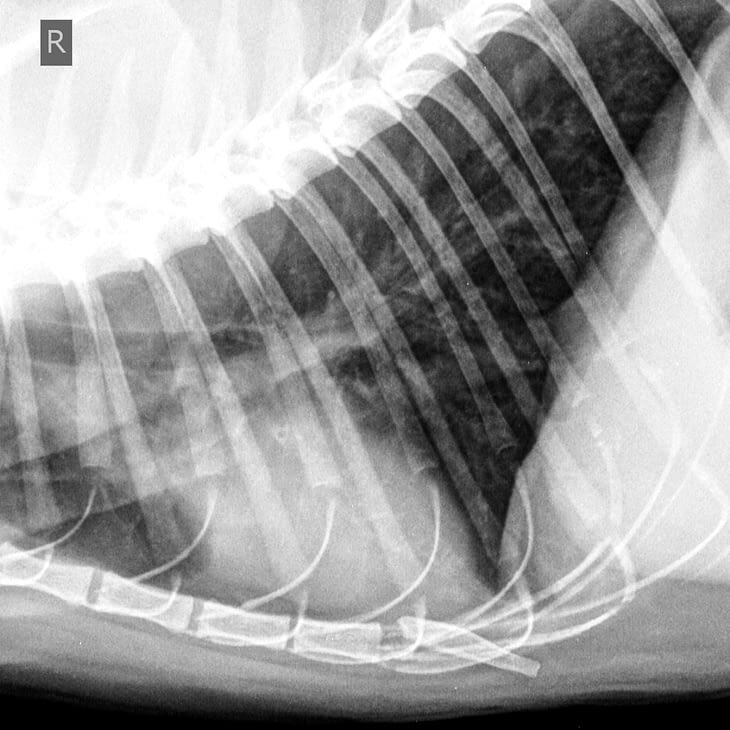

Кошка, 8 лет: мелкие метастазы в легких

Кошка, 8 лет, множественные метастазы в легких

Перед операцией животное надо обследовать на наличие метастазов в лимфатических узлах или легких. Для этого делается фронтальный снимок грудной клетки слева и справа. Два боковых рентгеновских снимка позволяют сделать наиболее достоверную оценку области грудной клетки. Только метастазы, диаметр которых превышает 0,5 см, хорошо распознаются на рентгеновском снимке. Если не видно никаких метастазов, опухоль хирургически удалятся под общей анестезией.